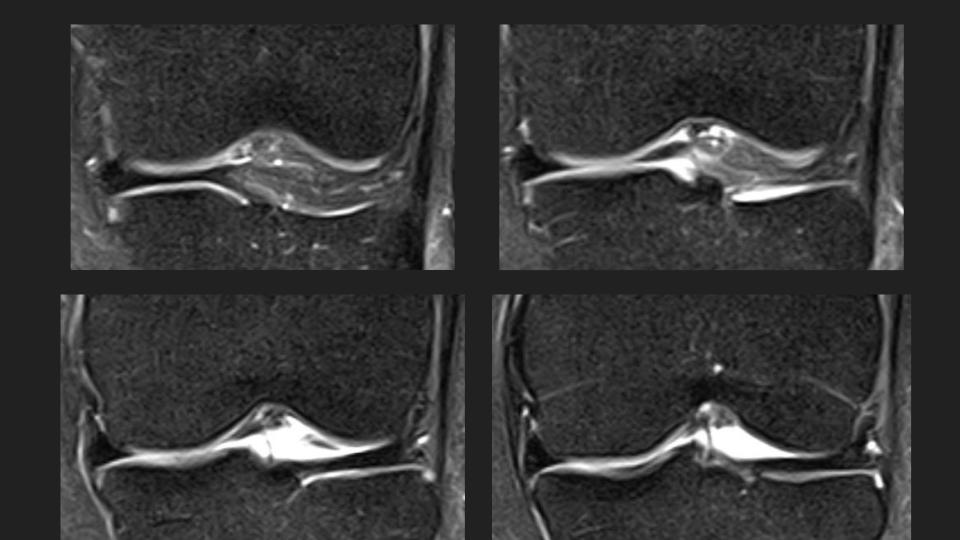

27M knee pain

This is an anteromedial meniscofemoral ligament. It looks alot like the relatively common ligamentum mucosum, but is is rare (approx 0.4% incidence) and inserts onto the central aspect of the anterior horn medial meniscus rather than the patella. It is eye-catching, but incidental and should not be resected. Reference article.

meniscofemoral ligament ( RID2806 )